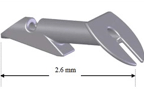

iStent®は開放隅角緑内障に対して眼圧を下降させる極低侵襲緑内障手術の際に使用されるMIGS(micro-invasive glaucoma surgery)デバイスです。単独での手術の際は自由診療となりますが、白内障手術と同時に行われる際には保険診療となります。

iStent®は、長さ横1mm縦0.12mmの非常に小さいデバイスです。緑内障手術は線維柱帯切除やEx-PRESS手術など各種の手術がありますが、今までの手術は目への侵襲が大きい手術でありました。

白内障手術の際に2.4mmの白内障手術創口からiStent®を線維柱帯にインプラントして、房水流出を妨げている線維柱帯に対して排出を改善し眼圧を下降させます。その為、侵襲の非常に少ない緑内障手術、極低侵襲緑内障手術として注目されております。臨床試験の結果では眼圧の下降と緑内障治療薬の低減が示されています。日本眼科学会HP[http://www.nichigan.or.jp/member/guideline/iStent.jsp]に詳細と論文がありますので、メリットデメリットなどご参考にして頂けますと幸いです。